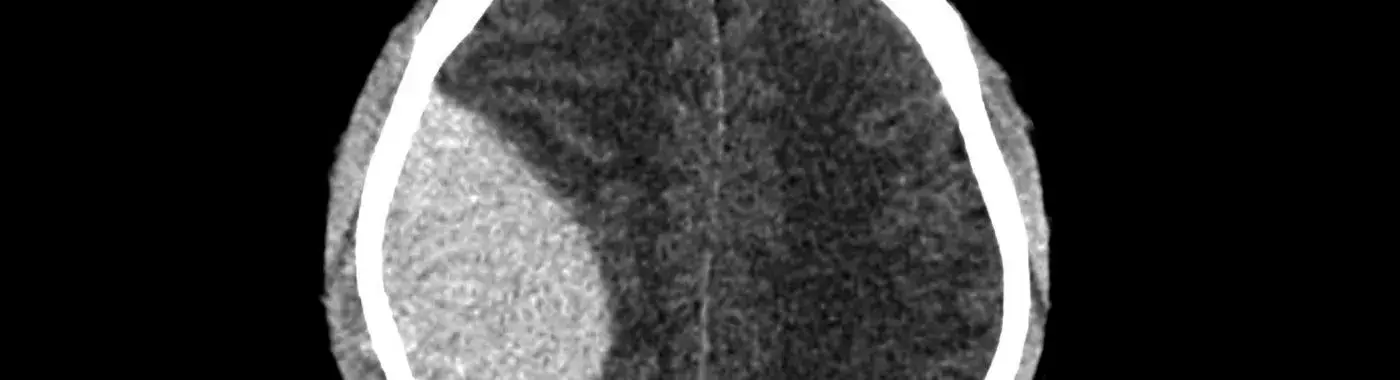

1. Imaging Studies: The primary diagnostic tool is a CT scan of the head, which can quickly reveal the presence of a hematoma. MRI may be used in certain cases for further evaluation.

Epidural hematoma (EDH) is a serious medical condition characterized by the accumulation of blood between the outer membrane of the brain (the dura mater) and the skull. This condition is often the result of a traumatic head injury and can lead to significant neurological impairment or even death if not promptly diagnosed and treated. Understanding epidural hematoma is crucial for recognizing its symptoms, causes, and treatment options, as timely intervention can greatly improve outcomes.

An epidural hematoma is a collection of blood that forms in the epidural space, which is the area between the dura mater and the skull. This space is normally filled with a small amount of fluid, but when a blood vessel ruptures—often due to trauma—blood can accumulate rapidly, leading to increased pressure on the brain. This pressure can cause brain damage and other serious complications if not addressed quickly.